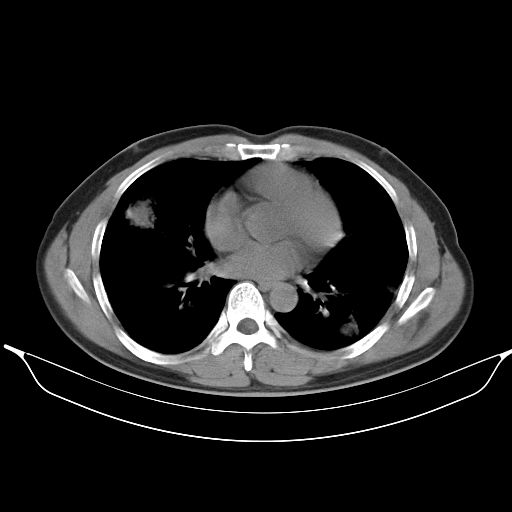

标题: CT25490:男,40岁,体检发现;无其它不适。 [打印本页]

标题: CT25490:男,40岁,体检发现;无其它不适。

考虑右下肺周围性肺癌并肺内多发转移,纵隔淋巴结转移!

支持 !考虑右下肺周围性肺癌并肺内多发转移,纵隔淋巴结转移,(气管前腔静脉后,隆突下,主动脉弓下都有了)

1、均为转移,原发灶不在肺内。2、肺癌肺转移。